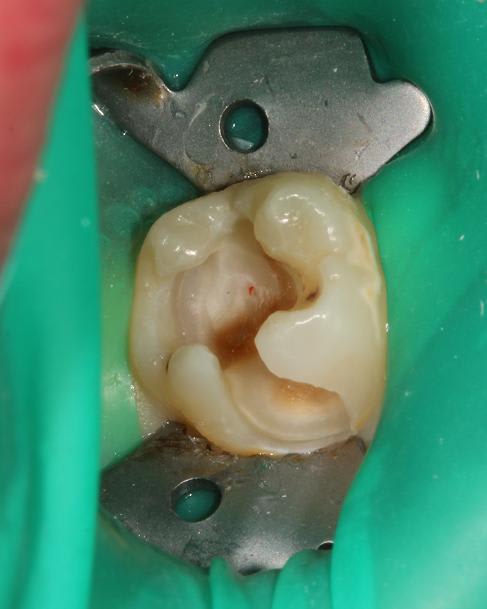

Quelques photos pour illustrer le sujet initial. Dommage que ces dents n'aient jamais eu de sealants.

Pour l'effraction pulpaire sur dent asymptomatique, je fais le protocole que Choixpeau avait mis sur le forum : hypochlorite puis adhésif directement au contact. Aucun problème à court terme pour le moment.

Si effraction plus importante : MTA.